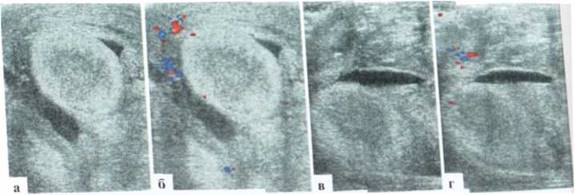

Особенности УЗИ при определении пола ребенка

Раздел: Идеи и советы